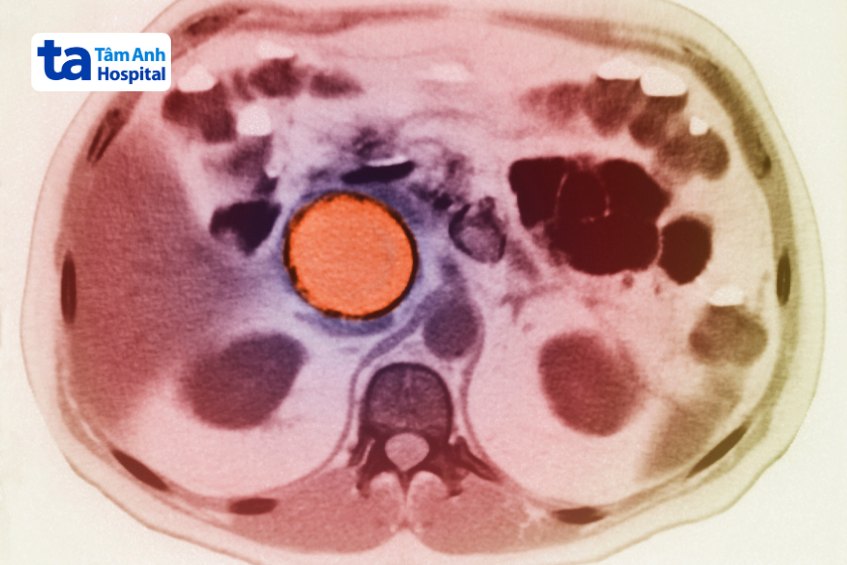

Thuật ngữ nang giả tụy khổng lồ là chỉ những nang giả tụy có kích thước trên 10 cm. Nhiều báo cáo cho thấy kích thước nang giả tụy có thể lên đến 35 cm. Trong năm 2023, Trung tâm Nội soi và Phẫu thuật Nội soi tiêu hóa, Bệnh viện Đa khoa Tâm Anh TP. Hồ Chí Minh đã tiếp nhận và điều trị thành công một ca bệnh nang giả tụy có kích thước 18 cm. Người bệnh nhập viện với những triệu chứng như chướng to bụng, căng tức bụng, hay nôn ói, ăn uống kém và suy nhược cơ thể.

Với những nang giả tụy có kích thước lớn trên 10 cm thì nang giả tụy có tự khỏi không? Câu trả lời là: Không thể. Lúc này, người bệnh cần can thiệp phẫu thuật. Lý do, ngoài những triệu chứng tiến triển nặng kéo dài, nang sẽ chiếm gần hết khu vực thượng vị, ảnh hưởng đến những cơ quan khác, tăng nguy cơ mắc các bệnh lý tiêu hóa. (2)